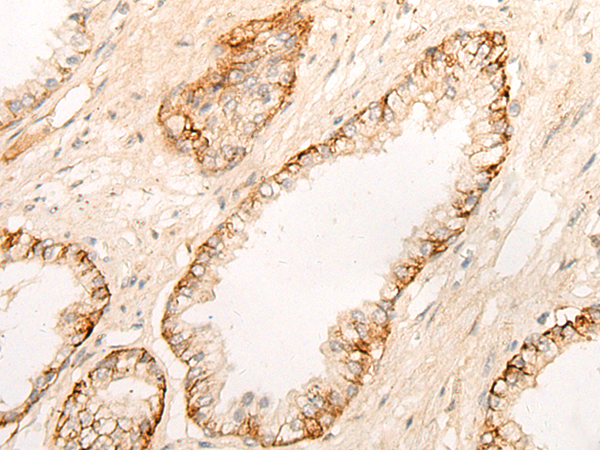

The image is immunohistochemistry of paraffin-embedded Human prostate cancer tissue using 47076(DPP9 Antibody) at dilution 1/20. (Original magnification: ?00)